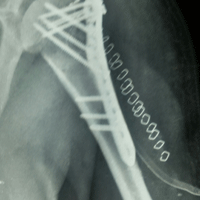

Case:14 Periprosthetic Fracture

60 years old patient with total knee replacement on left knee presented with open grade 1 injury. Debridement & slab given on emergency bases. Fixation with plate & screws done. Union was seen after 6 months.

Pre-Op AP

Pre-Op Lat.

Immdiate Post-op